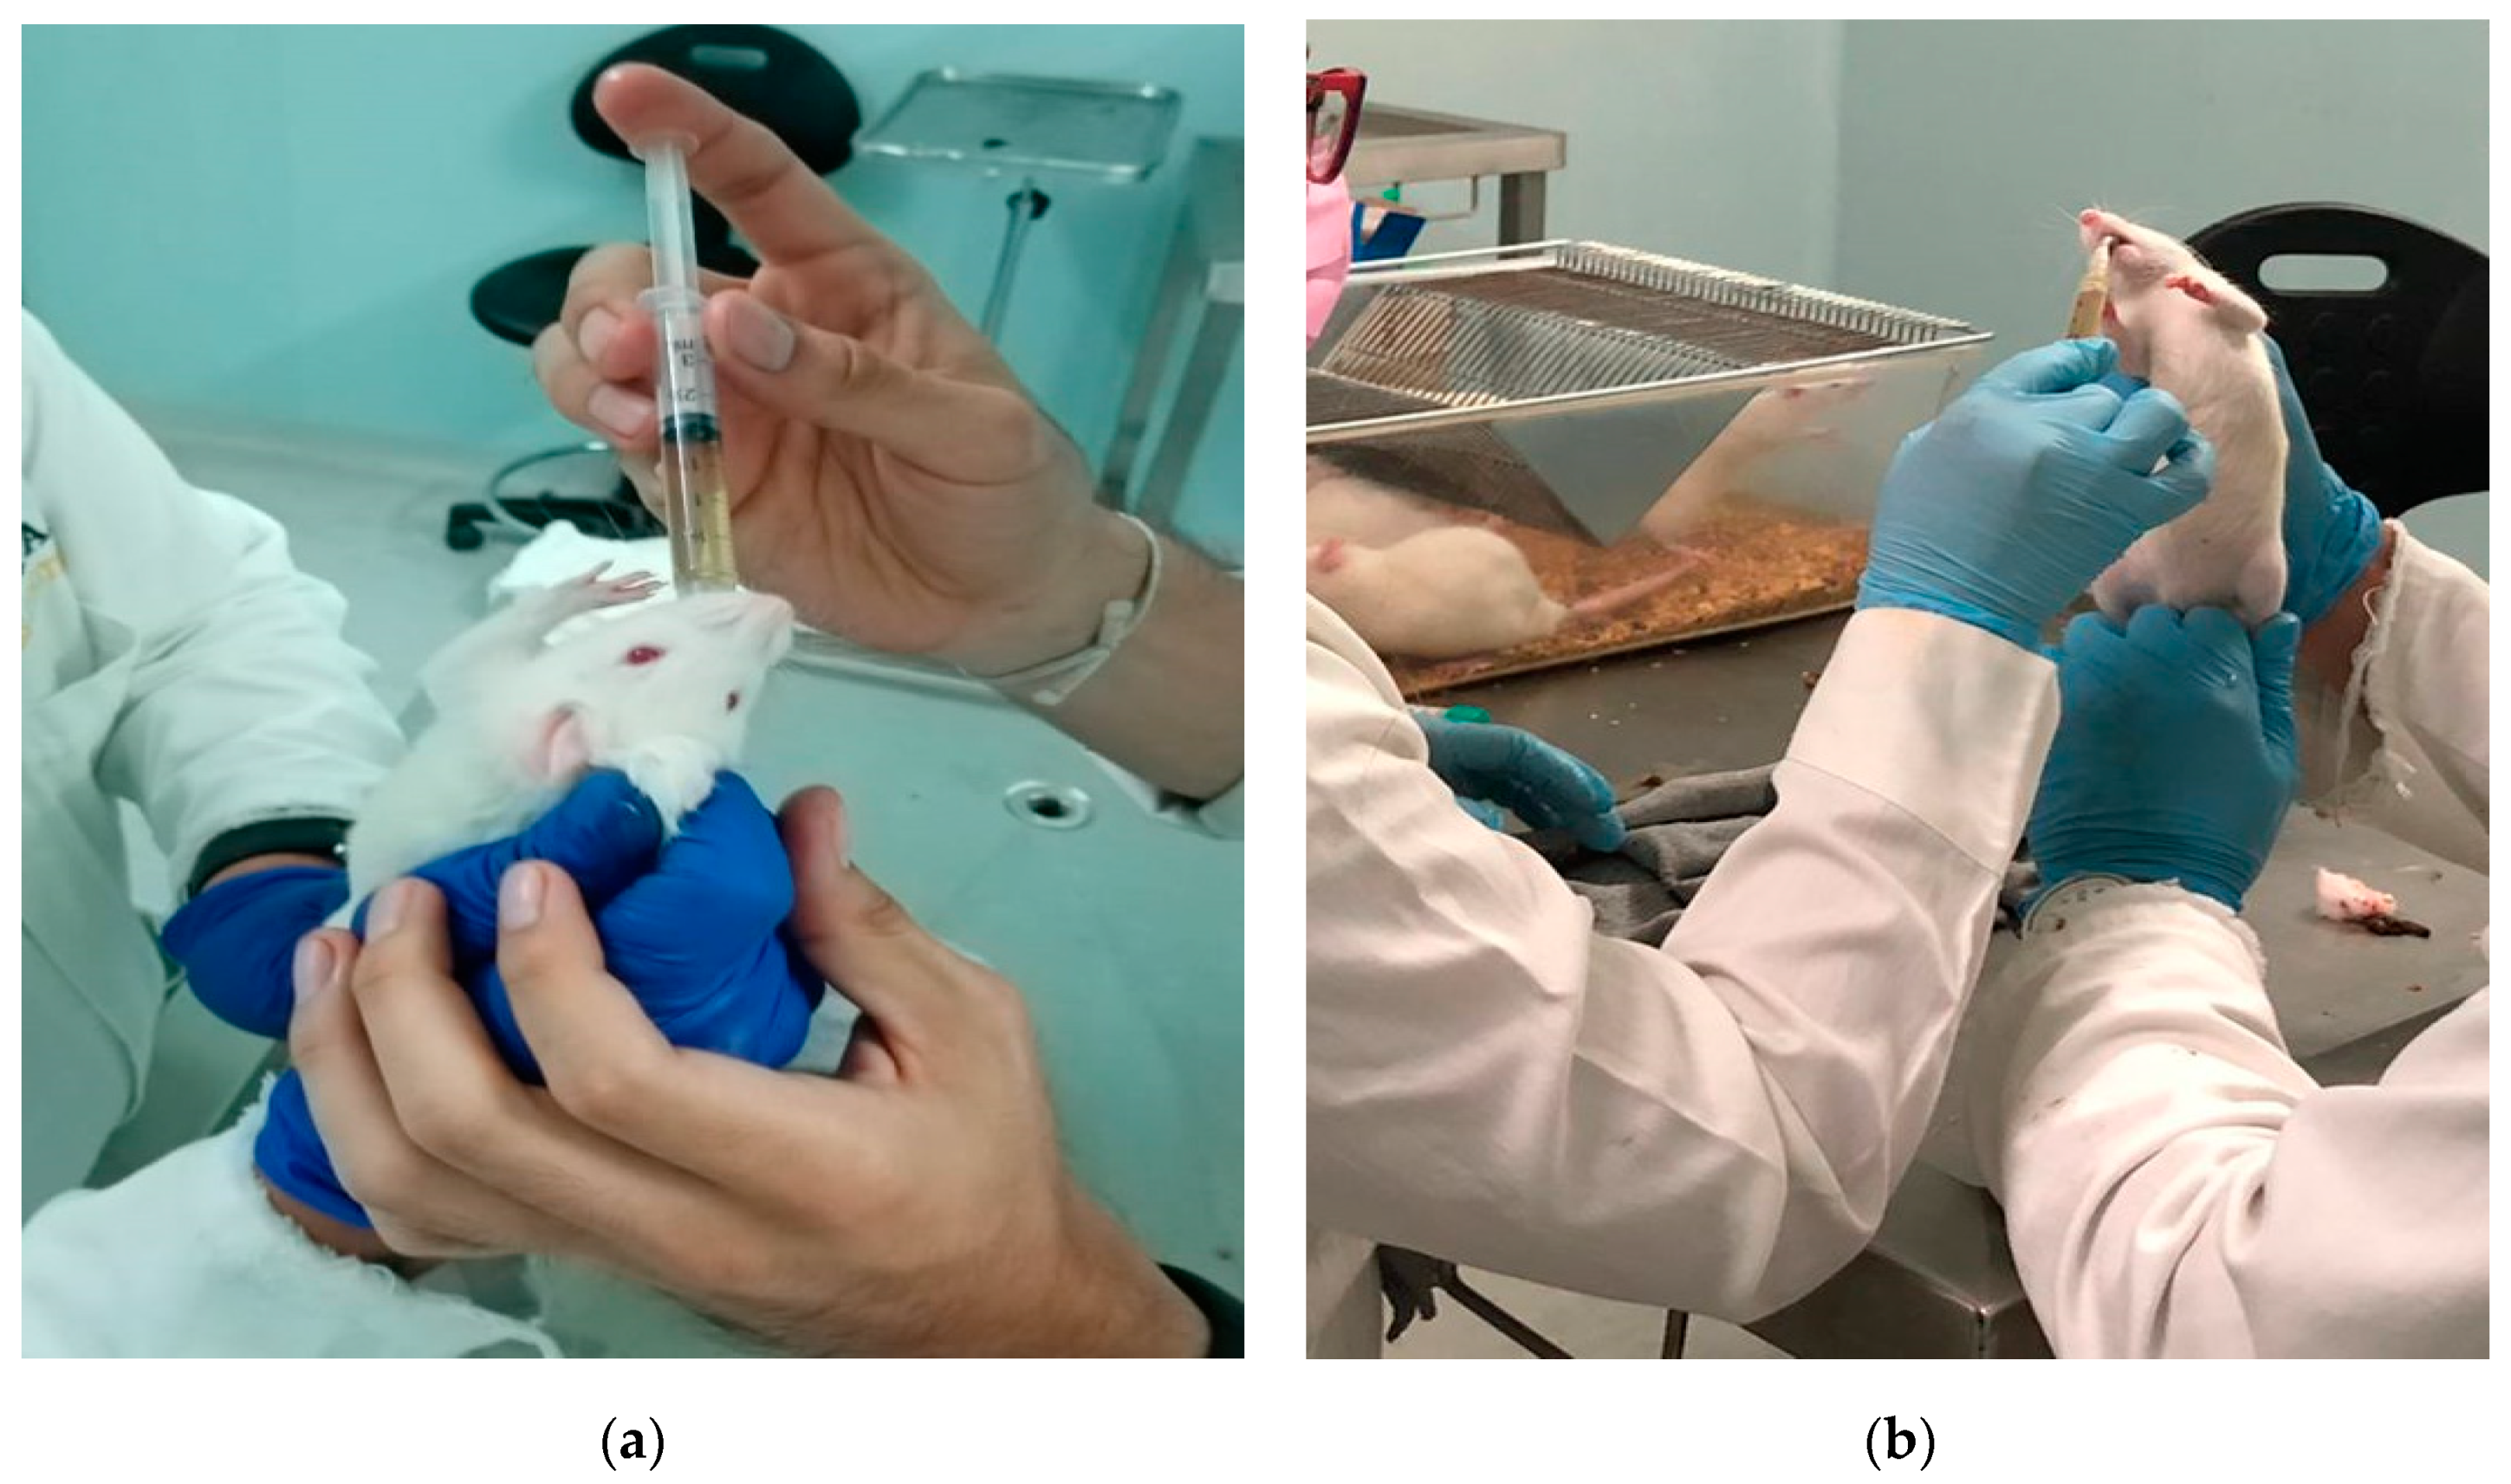

2.7. In Vivo Model

3.1.7. In Vivo Tests